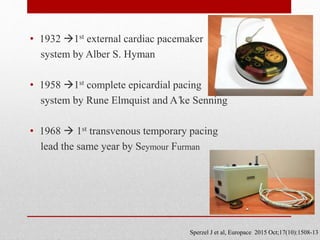

![A Leadless Intracardiac Transcatheter Pacing System

BACKGROUND

A leadless intracardiac transcatheter pacing system has been designed to avoid the need for a pacemaker pocket and

transvenous lead.

METHODS

A prospective multicenter study . The analysis of the primary end points began when 300 patients reached 6 months of

follow- up. The primary safety end point was freedom from system-related or procedure related major complications. The

primary efficacy end point was the percentage of patients with low and stable pacing capture thresholds at 6 months (≤2.0

V at a pulse width of 0.24 msec and an increase of ≤1.5 V from the time of implantation). The safety and efficacy end

points were evaluated against performance goals (based on historical data) of 83% and 80%, respectively. We also

performed a post hoc analysis in which the rates of major complications were compared with those in a control cohort of

2667 patients with transvenous pacemakers from six previously published studies.

RESULTS

The device was successfully implanted in 719 of 725 patients (99.2%). The Kaplan– Meier estimate of the rate of the

primary safety end point was 96.0% (95% confidence interval [CI], 93.9 to 97.3; P<0.001 for the comparison with the

safety performance goal of 83%); there were 28 major complications in 25 of 725 patients, and no dislodgements. The rate

of the primary efficacy end point was 98.3% (95% CI, 96.1 to 99.5; P<0.001 for the comparison with the efficacy

performance goal of 80%) among 292 of 297 patients with paired 6-month data. Although there were 28 major

complications in 25 patients, patients with transcatheter pacemakers had significantly fewer major complications than did

the control patients (hazard ratio, 0.49; 95% CI, 0.33 to 0.75; P = 0.001).

CONCLUSIONS

In this historical comparison study, the transcatheter pacemaker met the prespecified safety and efficacy goals; it had a

safety profile similar to that of a transvenous system while providing low and stable pacing thresholds

Reynolds D et al. NEJM. Feb 2016](https://image.slidesharecdn.com/leadlesspacemaker-170308163530/85/Leadless-pacemaker-25-320.jpg)